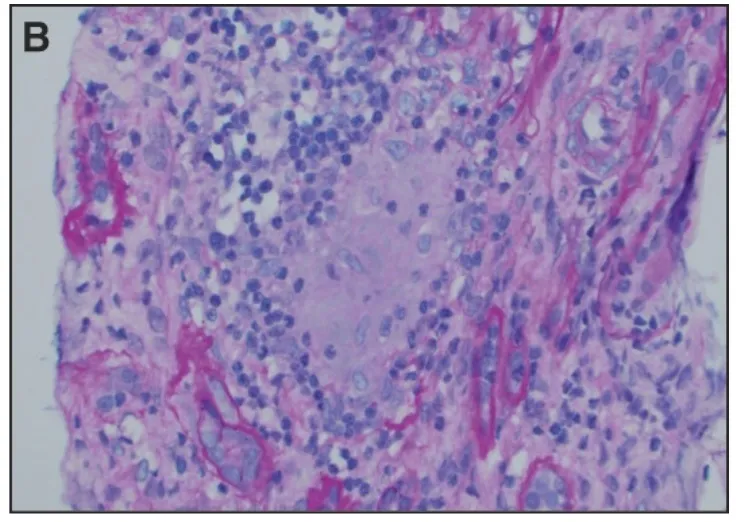

Alterações histológicas e abordagens práticas no cuidado renal dos pacientes com síndrome metabólica NÃO DIABÉTICOS

Alterações histológicas e abordagens práticas no cuidado renal dos pacientes com síndrome metabólica NÃO DIABÉTICOSA epidemia da Síndrome Metabólica pode impactar diretamente nos desfechos renais, confere esse estudo que apresenta dados histológicos interessantes para mostrar a importância desse tema

Luís Sette